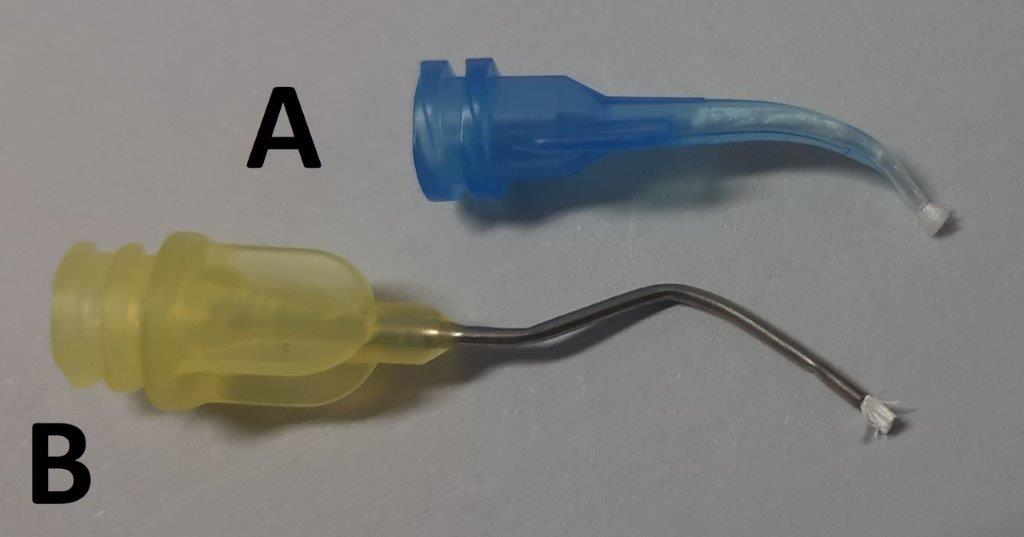

Optymalne rozwiązanie stanowi mała strzykawka, na którą można nakręcić aplikator zakończony pędzelkiem (ryc. 4-6). Takie rozwiązanie znacznie ułatwia aplikację preparatu i jego skuteczne działanie w wyniku dość intensywnego wcierania w miazgę.

Ryc. 5. Aplikatory Dental-Infusor (Ultradent, USA) zakończone pędzelkiem. A. Aplikator plastikowy; B. Aplikator metalowy.

Ryc. 6. Pędzelki zapewniające skuteczne wtarcie żelu hemostatycznego w kikuty miazgi. A. Aplikator Dental-Infusor plastikowy; B. Aplikator Dental-Infusor metalowy.